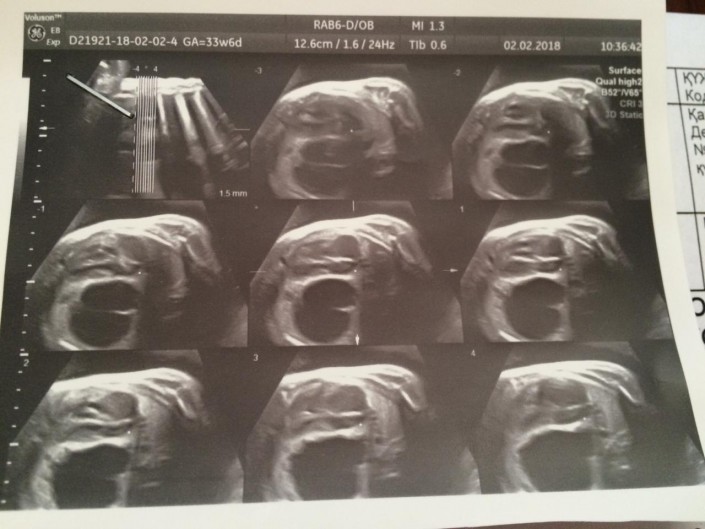

Снимок УЗИ. Киста в левом легком Яна